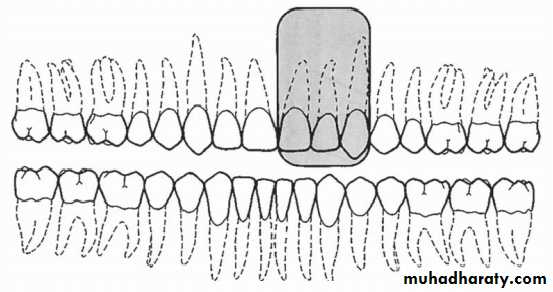

• The film is placed in the mouth parallel to the crown of both upper & lower teeth.

• The film stabilized when the patient bites on the bite-wing tab or bite-wing film holder.

• The central ray of the x-ray beam is directed through the contacts of the teeth, using a +10 degree vertical angulation.

+10o vertical angulation is used to compensate for the slight bend of the upper portion of the film and the tilt of the maxillary teeth.

Premolar bitewing. A, Film placement. B, Resultant radiograph.

AB

The molar-bitewing. A, Film placement. B, Resultant radiograph.

A

B